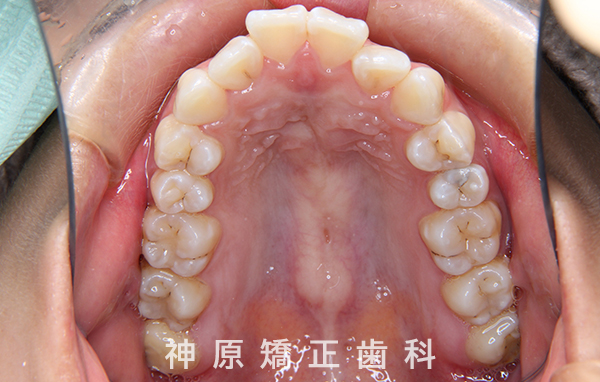

初診時

口元の突出感と下の歯並びの乱れを改善するため、小臼歯を抜歯することにしました。抜いたスペースを利用して、前歯をできるだけ後ろに移動させるため、上下に歯科矯正用アンカースクリューを使用する計画を立てました。治療の目標について同意を得た後、矯正治療を開始しました。歯の動きが順調で、1年9カ月で治療が完了しました。その結果、側貌はE-lineに調和したバランスの良い仕上がりになりました。